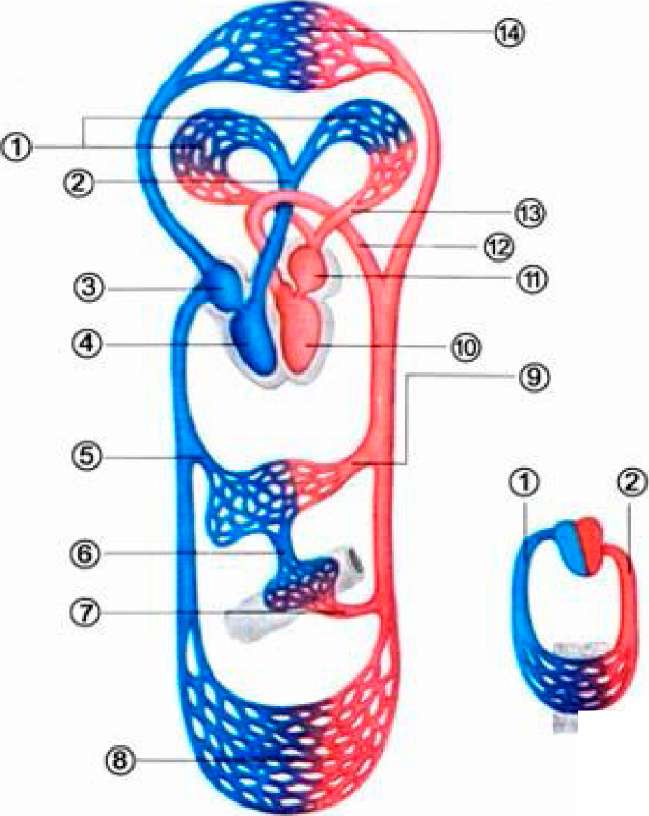

Кровеносная система человека: структура и функции

Раздел: Идеи и советы